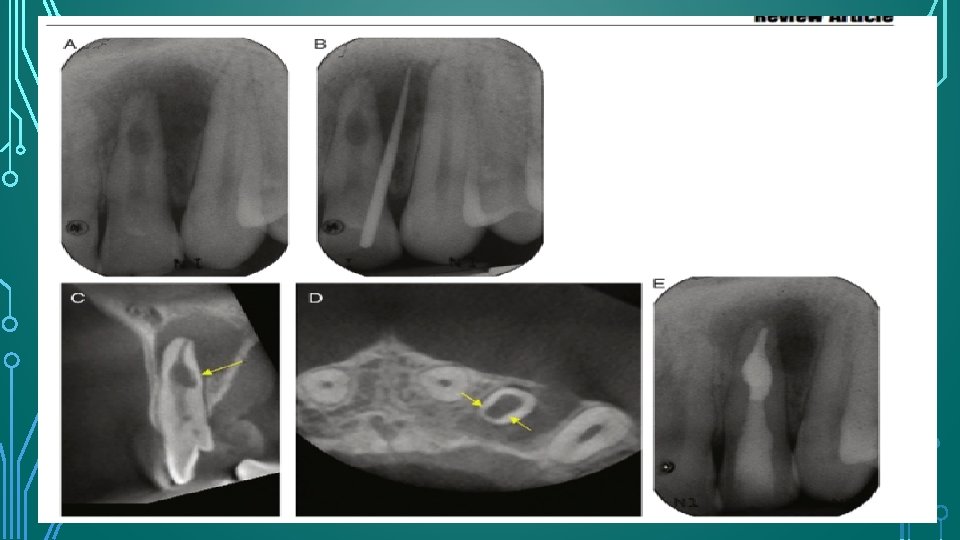

RADIOGRAPHIC FEATURES AND DIAGNOSIS • Gartner – radiolucency of uniform density that have a smooth outline and are symmetrically distributed over the root of the affected tooth • The outline of the root canal wall should not be traceable through the resorption defect because the root canal wall balloons out. • Oval, circumscribed radiolucency in continuity with the root canal wall. • Internal replacement root resorption – somewhat mottled or clouded appearance as a result of the radiopaque nature of the calcified material occupying the lesion.

MANAGEMENT Check prognosis Root canal treatment Remove the intraradicular bacteria and disinfect the root canal system Intracanal antibacterial medicament should be used to further reduce the microbial load and improve the disinfection of the root canal space Obturation with Obtura II and Microseal (MS) thermoplastic

Because root sealers shrink on setting and degrade to varying degrees in the presence of moisture , fillings with higher GP/ sealer ratios reduce the risk of void formation and leakage of contaminants into the root canal system. If perforation has occurred , MTA should be considered the material of choice to repair the root wall.